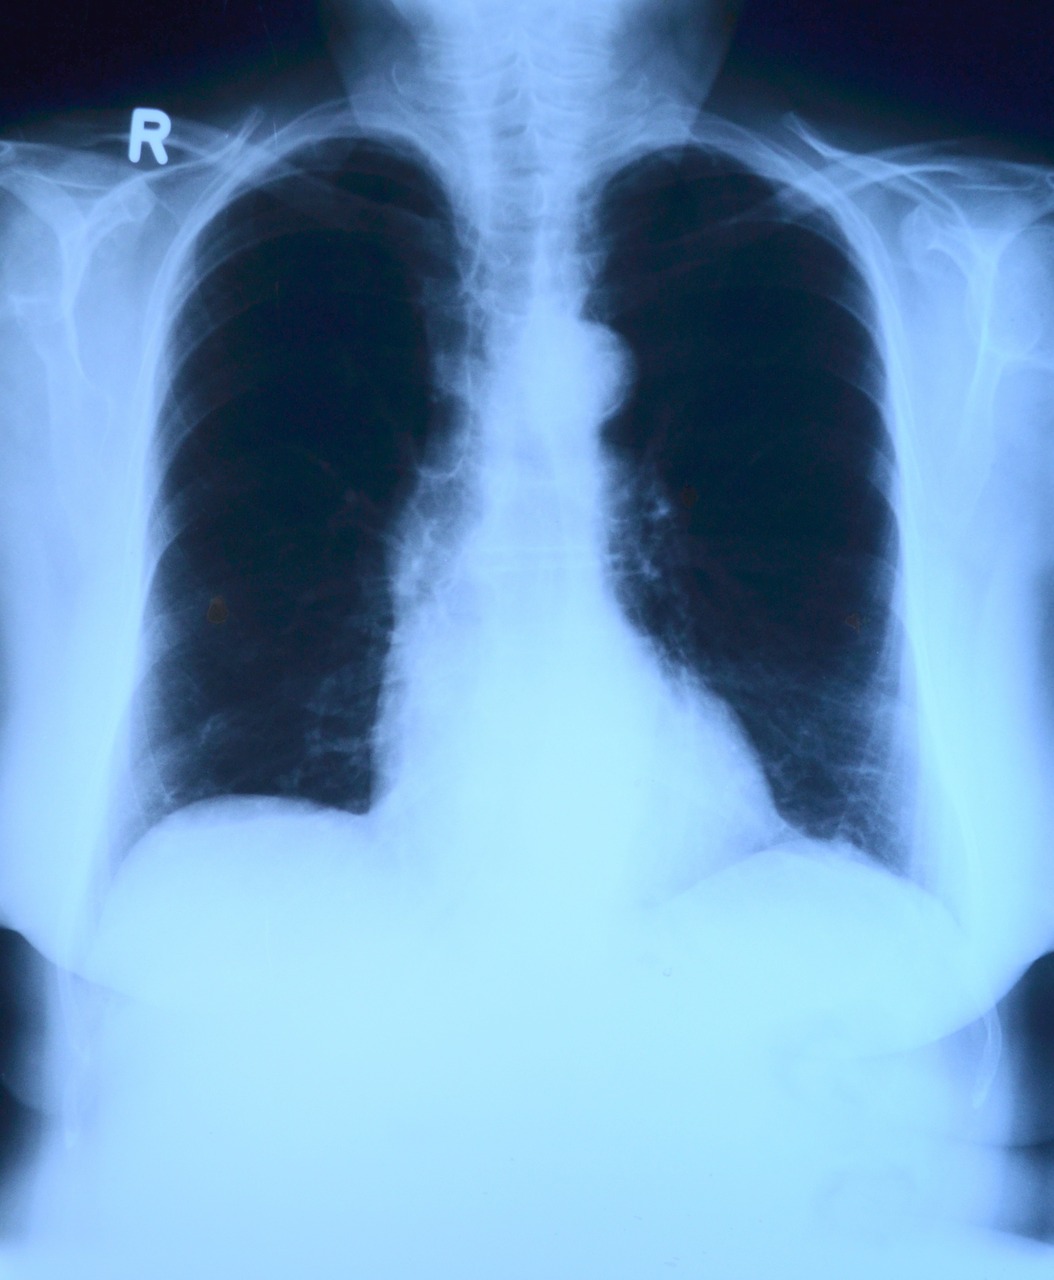

Mieszkańcy coraz częściej pytają, czy pojawiające się informacje o zamiarze likwidacji noworudzkiej pracowni RTG są prawdziwe. Niepokój naszych pacjentów nie powinien dziwić, tym bardziej, że został im już zabrany oddział wewnętrzny, który do dziś jest zawieszony. - Na dzień dzisiejszy, nie jest planowana likwidacja pracowni RTG w Nowej Rudzie – uspokaja Bartosz Wojciechowski z kłodzkiego starostwa. Potrzebny nowy rentgen Na razie likwidacji pracowni nie będzie. Nie zmienia to faktu, że aparat rentgenowski, którym dziś bada się pacjentów posłuży nam jedynie jeszcze przez kilka miesięcy. Później traci tzw. akredytację i potrzebny będzie nowy sprzęt. Pytanie co w związku z tym ma zamiar zrobić dyrekcja kłodzkiego szpitala? - Funkcjonujący w pracowni RTG w Nowej Rudzie aparat został zmodernizowany w 2013 roku i w związku z tym należałoby rozważyć zakup nowego lub wykonywanie badań na innym aparacie, który zapewniłby bezpieczeństwo pacjentom, u których wykonywane są badania radiologiczne - przyznaje Jadwiga Radziejewska, dyrektor kłodzkiego szpitala.